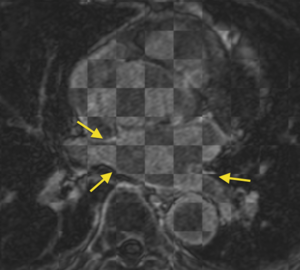

User-chosen fiducial-based approach

• We need a more accurate registration pipeline for the pulmonary veins.

• To explore ideas for establishing correspondence (via registration or other means) between points on the surface of the pulmonary veins (PV) and PV antrum near the left atrium in pre-RF-ablation DEMRI images with post-RF-ablation DEMRI images to within about 2 mm precision. This may be an impossible task (or impossible to validate the results, anyway), but there are many important application areas for AF research and clinical treatment if we can do it. For the Project Week, our main goal is to explore possibilities with available NAMIC expertise and Slicer tools during the meeting. If a likely algorithm can be identified, we will plan a Slicer module to implement it.

• Related to the idea of registration and correspondence in the PV, we have some specific ideas for how to effectively visualize and interact with off-axis, 2D slices through registered (in the sense of the aforementioned surface correspondence to within 2mm) pre- and post- RF ablation DEMRI images. Our specific needs are to present a physician with side-by-side views of corresponding anatomy on which to make manual measurements and qualitative analyses. The visualization tools we have in mind do not seem to easily fit within the constraints of a current Slicer module, so we may need to talk about additional Slicer core functionality.